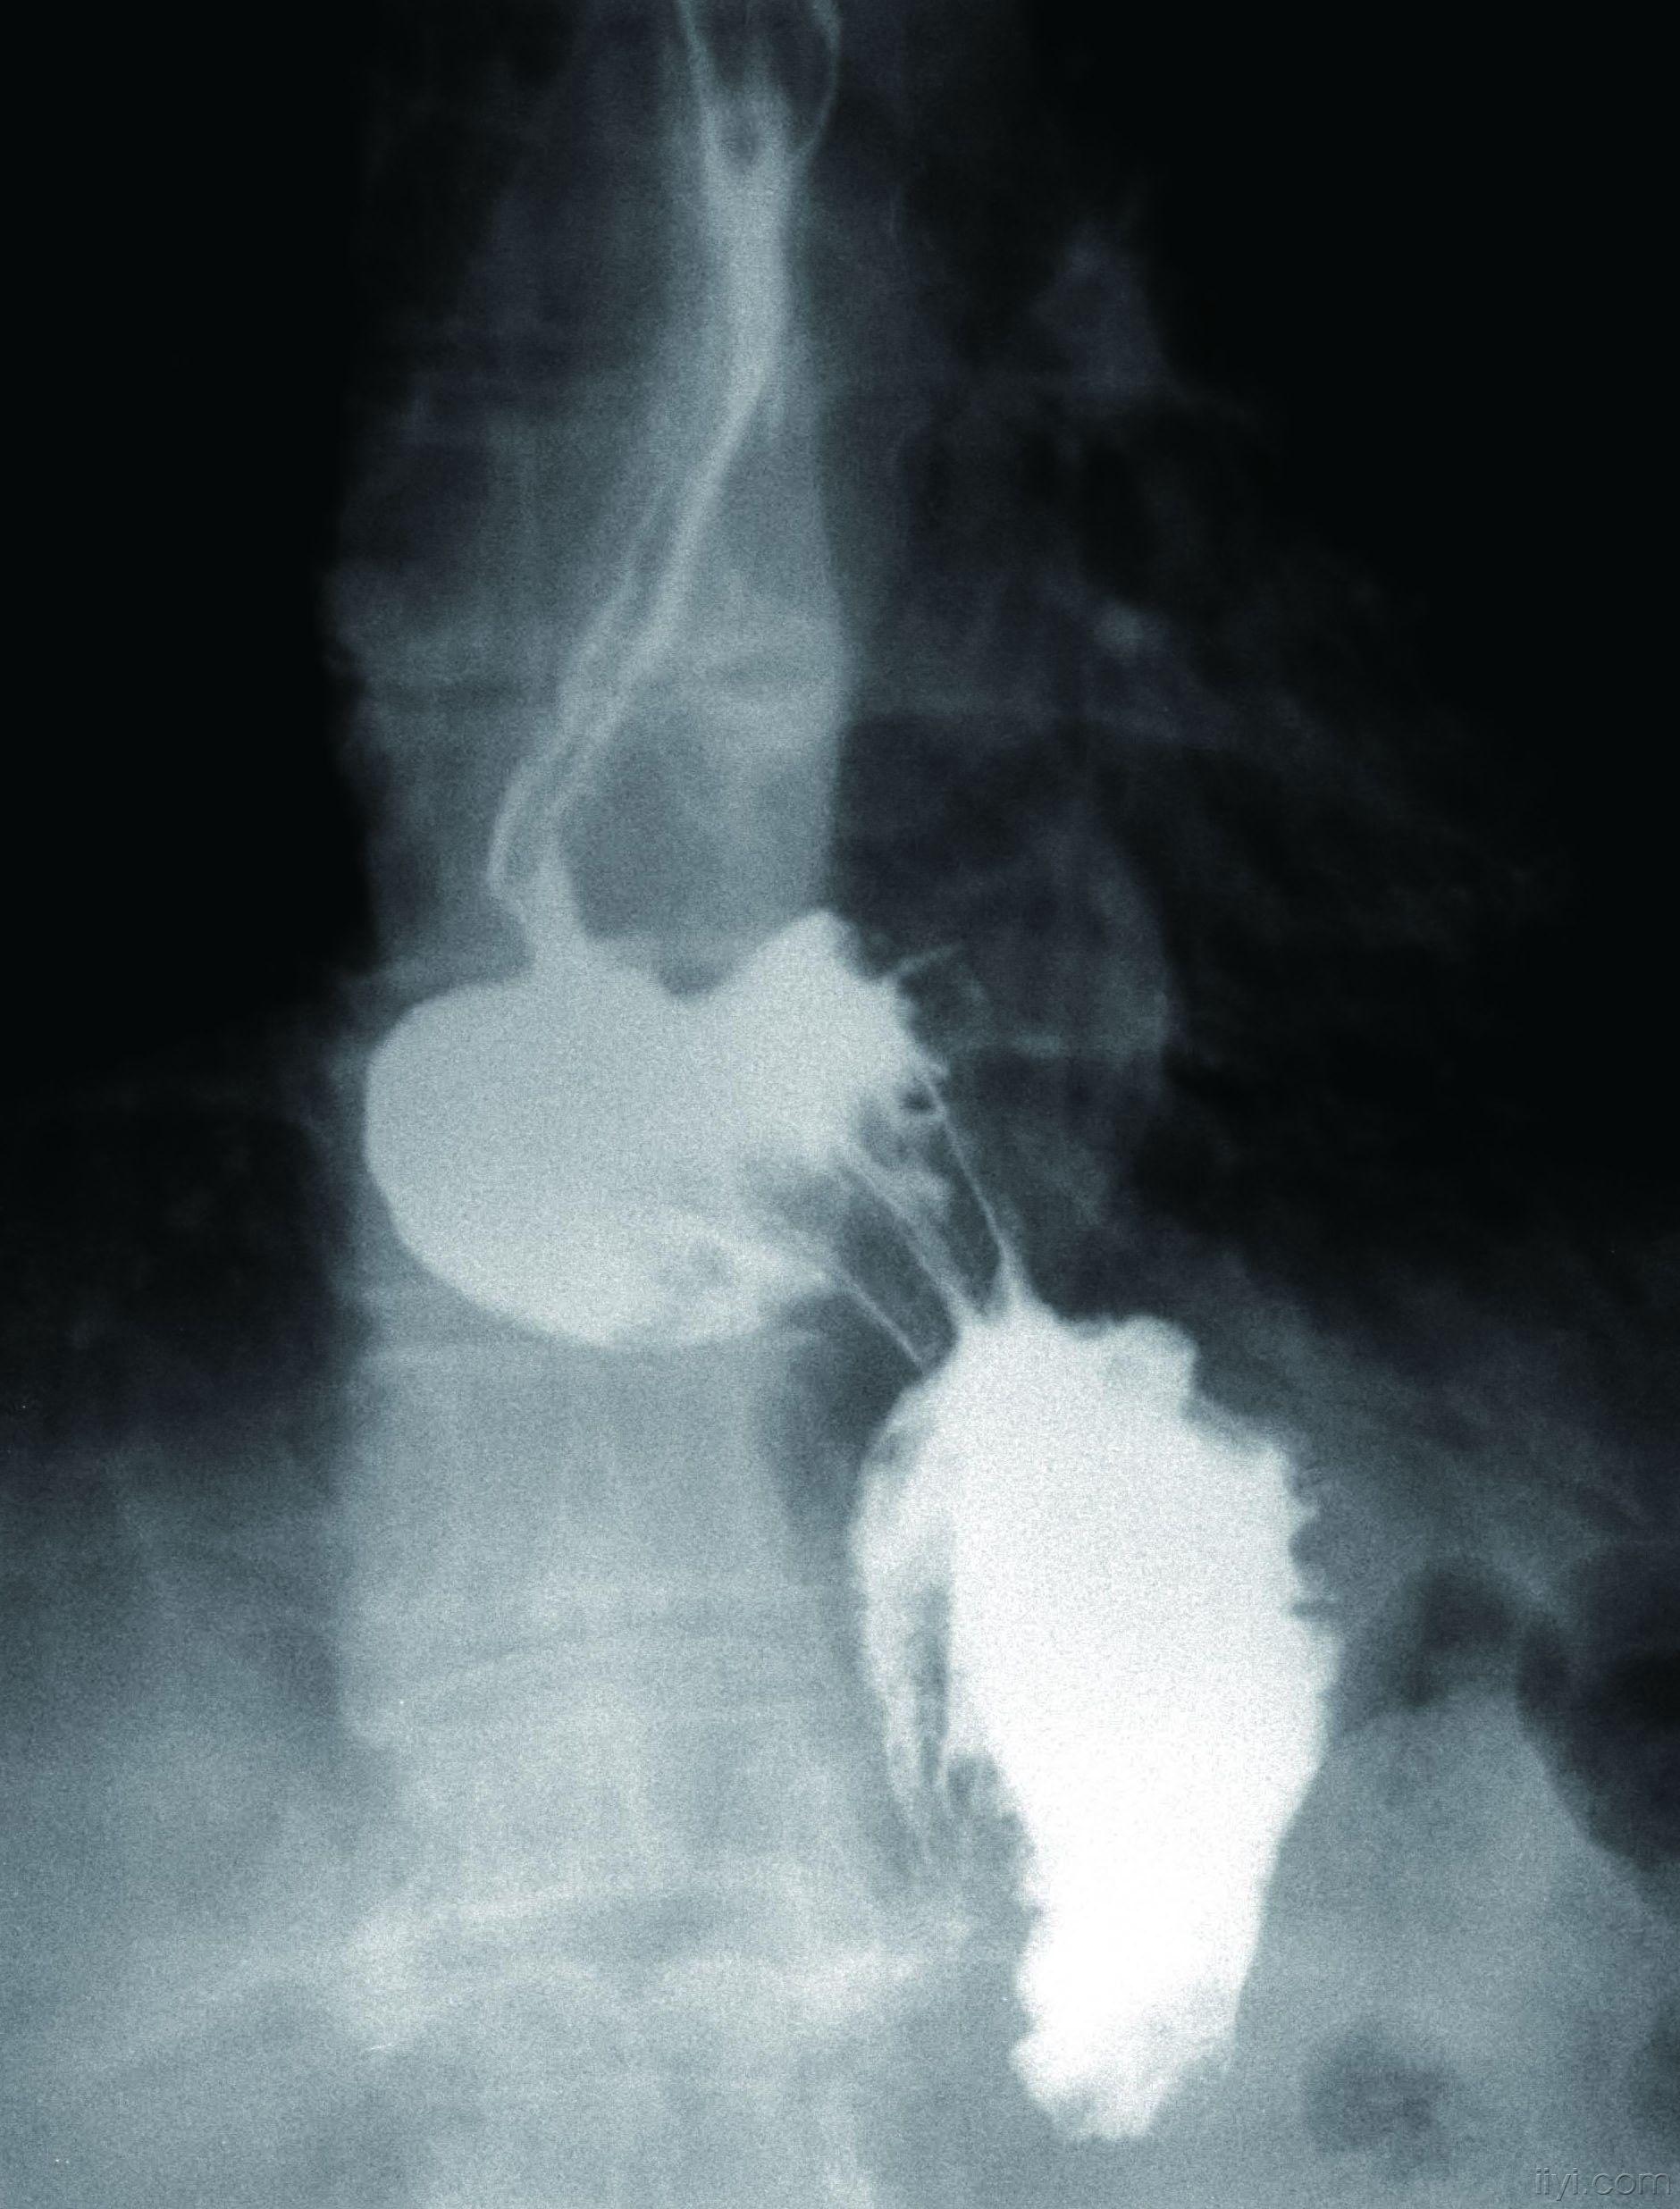

食管裂孔疝造影

哈医大二院胸外科经典病例之食管裂孔疝

市二院放射科查出一例巨大食管裂孔疝伴胃扭转罕见病例